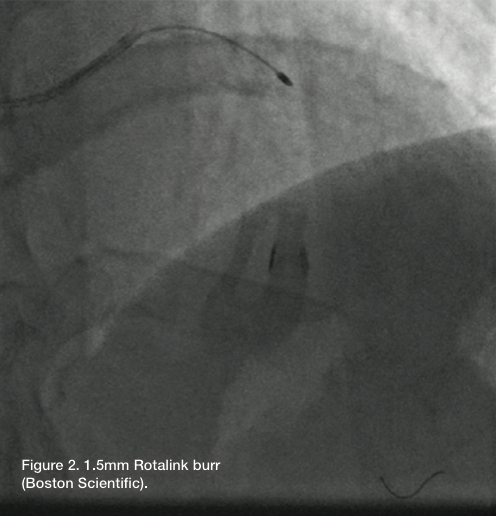

A 1.5mm burr (RotaLink, Boston Scientific) was used to perform rotational atherectomy of the LAD. Total run time was about 30 seconds. Following rotational atherectomy, the over-the-wire balloon was advanced distally and the RotaWire exchanged for a Wiggle wire (Abbott Vascular). We advanced the Runthrough wire as a buddy wire (removed prior to rotational atherectomy).